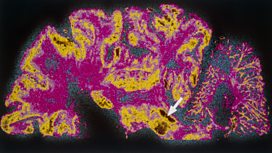

Could a drug used to treat diabetes give hope to those who have Parkinson's disease?